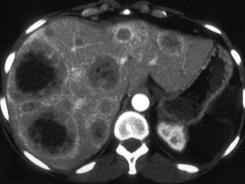

女,65岁,食管癌术后2年,CT检查如图,应诊断为 ( )A、肝囊肿B、肝结核C、肝转移瘤D、肝棘球蚴病E、肝脓肿

问题 女,65岁,食管癌术后2年,CT检查如图,应诊断为 ( )

选项 A、肝囊肿 B、肝结核 C、肝转移瘤 D、肝棘球蚴病 E、肝脓肿

答案 C